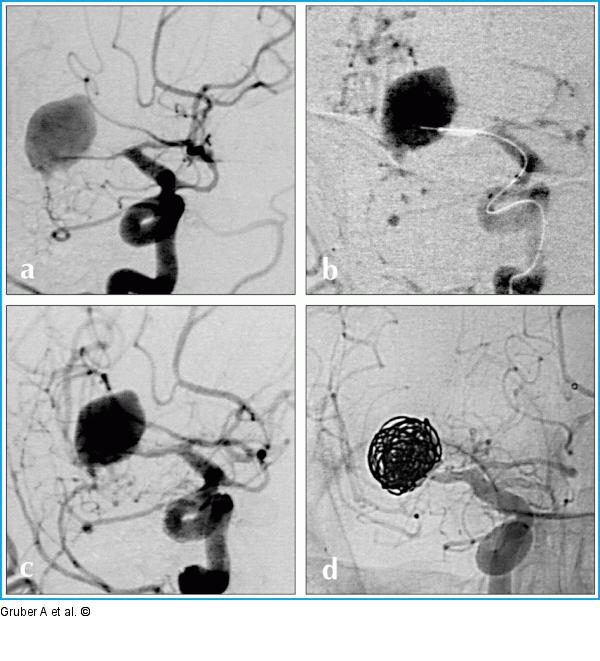

Abbildung 8a-d: Ballon-Angioplastie Präinterventionelle Ballon-Angioplastie. Angiogramme der rechten A. carotis interna zeigen einen schweren segmentalen posthämorrhagischen Vasospasmus des Mediahauptstammes am Tag 7 nach aneurysmatischer Subarachnoidalblutung (a). Eine chirurgische Versorgung des Aneurysmas ist nicht bzw. nur unter erheblicher Morbidität möglich. Nach Ballon-Angioplastie des spastischen Mediahauptstammes (b) und merklicher Zunahme des Gefäßkalibers (c) ist eine sichere Begehung des Aneurysmas mit einem Mikrokatheter und selektive Coil-Embolisation (d) möglich. |

Präinterventionelle Ballon-Angioplastie. Angiogramme der rechten A. carotis interna zeigen einen schweren segmentalen posthämorrhagischen Vasospasmus des Mediahauptstammes am Tag 7 nach aneurysmatischer Subarachnoidalblutung (a). Eine chirurgische Versorgung des Aneurysmas ist nicht bzw. nur unter erheblicher Morbidität möglich. Nach Ballon-Angioplastie des spastischen Mediahauptstammes (b) und merklicher Zunahme des Gefäßkalibers (c) ist eine sichere Begehung des Aneurysmas mit einem Mikrokatheter und selektive Coil-Embolisation (d) möglich. |